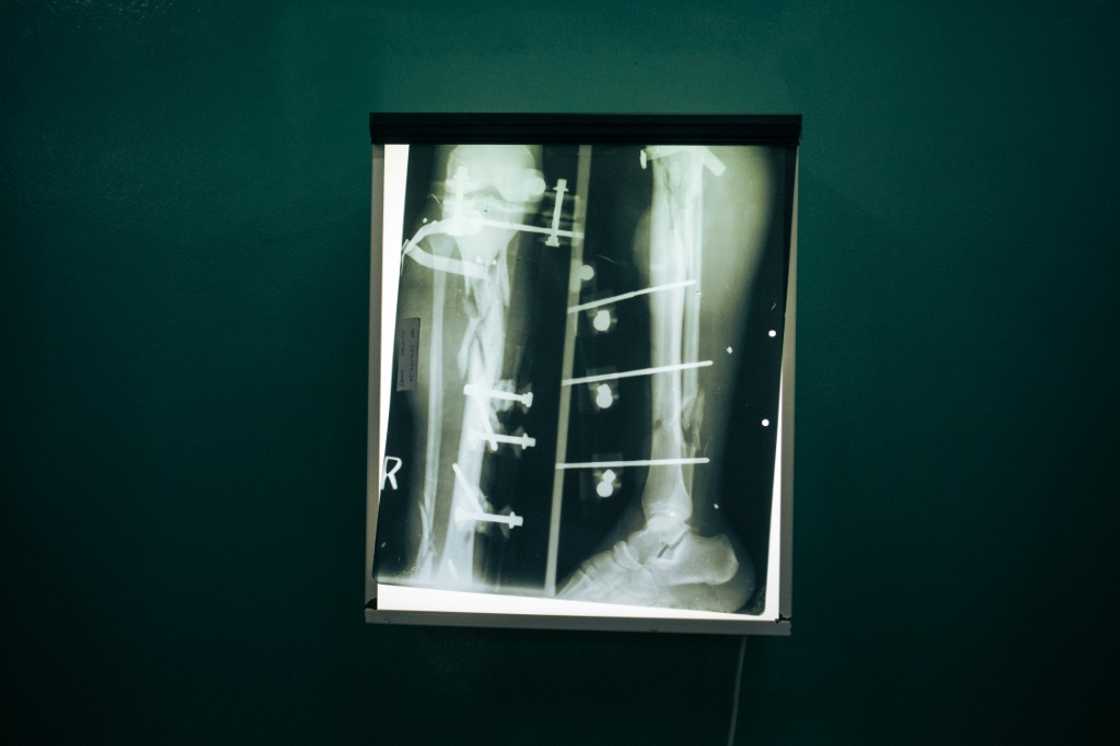

Dozens of bandaged patients lounge on beds in a hushed hospital ward in eastern Democratic Republic of Congo, groans of pain occasionally breaking the silence.

Many on the ward -- which reeked of sweat -- were gravely wounded. Some had lost limbs in the brutal fighting. Others a jaw.

Doctors performed surgery on 271 patients in June alone, according to the hospital, with a third of that number receiving treatment for gunshot wounds.

One surgeon, removing his blood-stained gloves after performing an operation, said that he and colleagues were being forced to prioritise care based on "chances of survival".

"It's very difficult," he said, but noted that the situation had been far worse at the beginning of July.